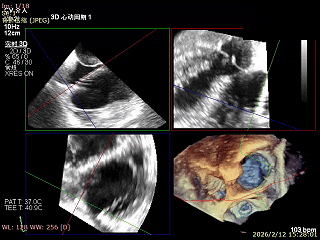

二尖瓣术前评估

复查TTE及TEE检查进一步评估二尖瓣情况。明确为AFMR,二尖瓣功能性反流,2区瓣叶运动,重度FMR(3+),肺静脉逆向血流;2区后叶长度13 mm,2区前叶长度20mm,AP径37mm,瓣口面积4.08cm²,房间隔高度4.5cm,瓣叶无钙化,二尖瓣瓣膜条件适合行TEER手术。

二尖瓣2区功能性反流

二尖瓣三维视图

2区彩色血流